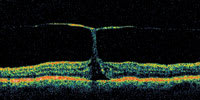

| Figure 3. This patient has vision of 20/30, but has an early apparent peeling of the inner retina along one side of the fovea. This may represent a laterally ruptured cyst and may or may not represent an early macular hole formation. |

A central clinical challenge has been accurately diagnosing early macular holes which may be mimicked by many other conditions.34,35 No imaging modality has enhanced our diagnostic capability more than the OCT; superior imaging capabilities have improved diagnostic accuracy, clinical monitoring, and postoperative assessment.36-38 The OCT unequivocally demonstrates early stages of full-thickness macular holes (Figure 1), and allows distinction of pseudohole and pre-macular hole conditions in almost all instances. Fluid accumulation in early, presumed pre-macular hole stages have been corroborated by OCT observations (Figure 2). Serial images have been reported showing the progression from apparent impending macular holes to full thickness macular holes.39-42 It has depicted many other configurations that might be in the spectrum of lamellar or pre-macular hole conditions (Figure 3 and 4).

Regardless of the initiating mechanism, once the vitreous separates, an early (occult) macular hole could repair itself (especially if very small) via glial proliferation with little or no clinical symptoms or signs. If a full-thickness macular hole first presents as reopening of a previously undetected, self-healed macular hole, this could account for the predominance of (hyperplastic) Mueller cells and glial cells found in the removed opercula. If the discontinuity is too large, migration of reparative, proliferating glial cells is impeded,57 so a macular hole would enlarge as the glial cells which migrated around the hole edge onto the perifoveal internal limiting membrane progressively contract. The hydration theory is a novel concept that describes a mechanism by which a tiny dehiscence might permit increasing degrees of perifoveal cystic changes, and subsequently a dehiscence of a larger unit of inner retina (Figure 3).58